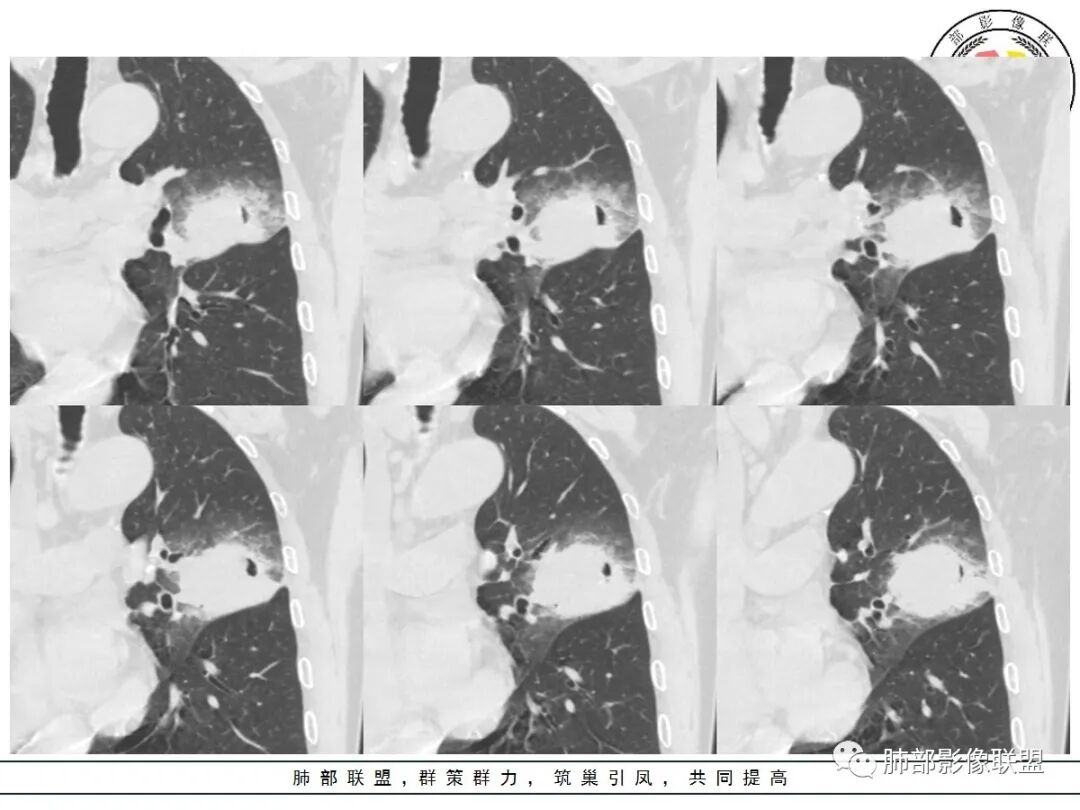

这三个月后的

发了后面这个,就不用纠结了,直接秒了。

大雄:

我只是要告诉大家,不是二元,就是肿瘤,没有什么感染,磨玻璃都没消失。

@小赵 这个不一定是粘液,很可能还是周围癌性浸润。看术前复查,原磨玻璃区呈明显小叶间隔增厚改变了。说明还是癌性淋巴浸润。

@温附一影像科,傅钢泽 应该是STA(气腔播散)加癌性淋巴管炎。

反思,恶性膨隆,远端空洞,强化坏死不均,里面血管似乎也是增粗,边界不清,似乎有侵犯。坏死还是边界不清。

5、周围磨玻璃,3个月后逐渐转为密实,应符合当初附壁生长为主,且逐渐向实体成分转换。

6、病变长轴平行且受限于胸膜,外围大内带小,符合外朝内发展病变。“腔内结节状明显强化”加之支气管改变有力支持新生物诊断。如此大范围边界不清的磨玻璃影让人浮想联翩。如此大范围病灶,肺门纵隔未见肿大淋巴结也让人意外。

12、前后对比进展:病灶增大、GGO区实变。